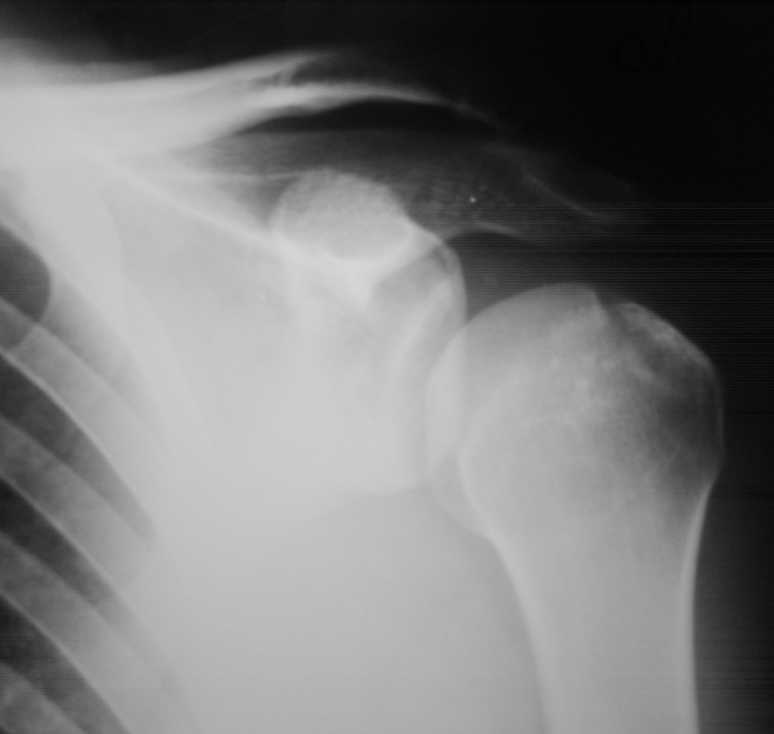

Падение на очередной гонке. По рассказу пациента произошел вывих плеча,

который доблестные мед. работники города Саранска вправили "наживую"

прямо на стадионе. Больного не фиксировали. По приезду зафиксировали

плечо в наружной ротации (см. фото). Сделали Кт (На серии КТ с толщиной

срезов 3 мм в левой плечевой кости определяется отрыв большого бугорка,

определяется линейный перелом клювовидного отростка левой лопатки без

смещения отломков (стрелки). В полости сустава- небольшое количество

жидкости. В головке плечевой кости определяется эностоз. Определяется

краевые костные разрастания акромиального конца ключицы. Заключение:

перелом левой лопатки и плечевой кости.) Возникли вопросы по дальнейшей